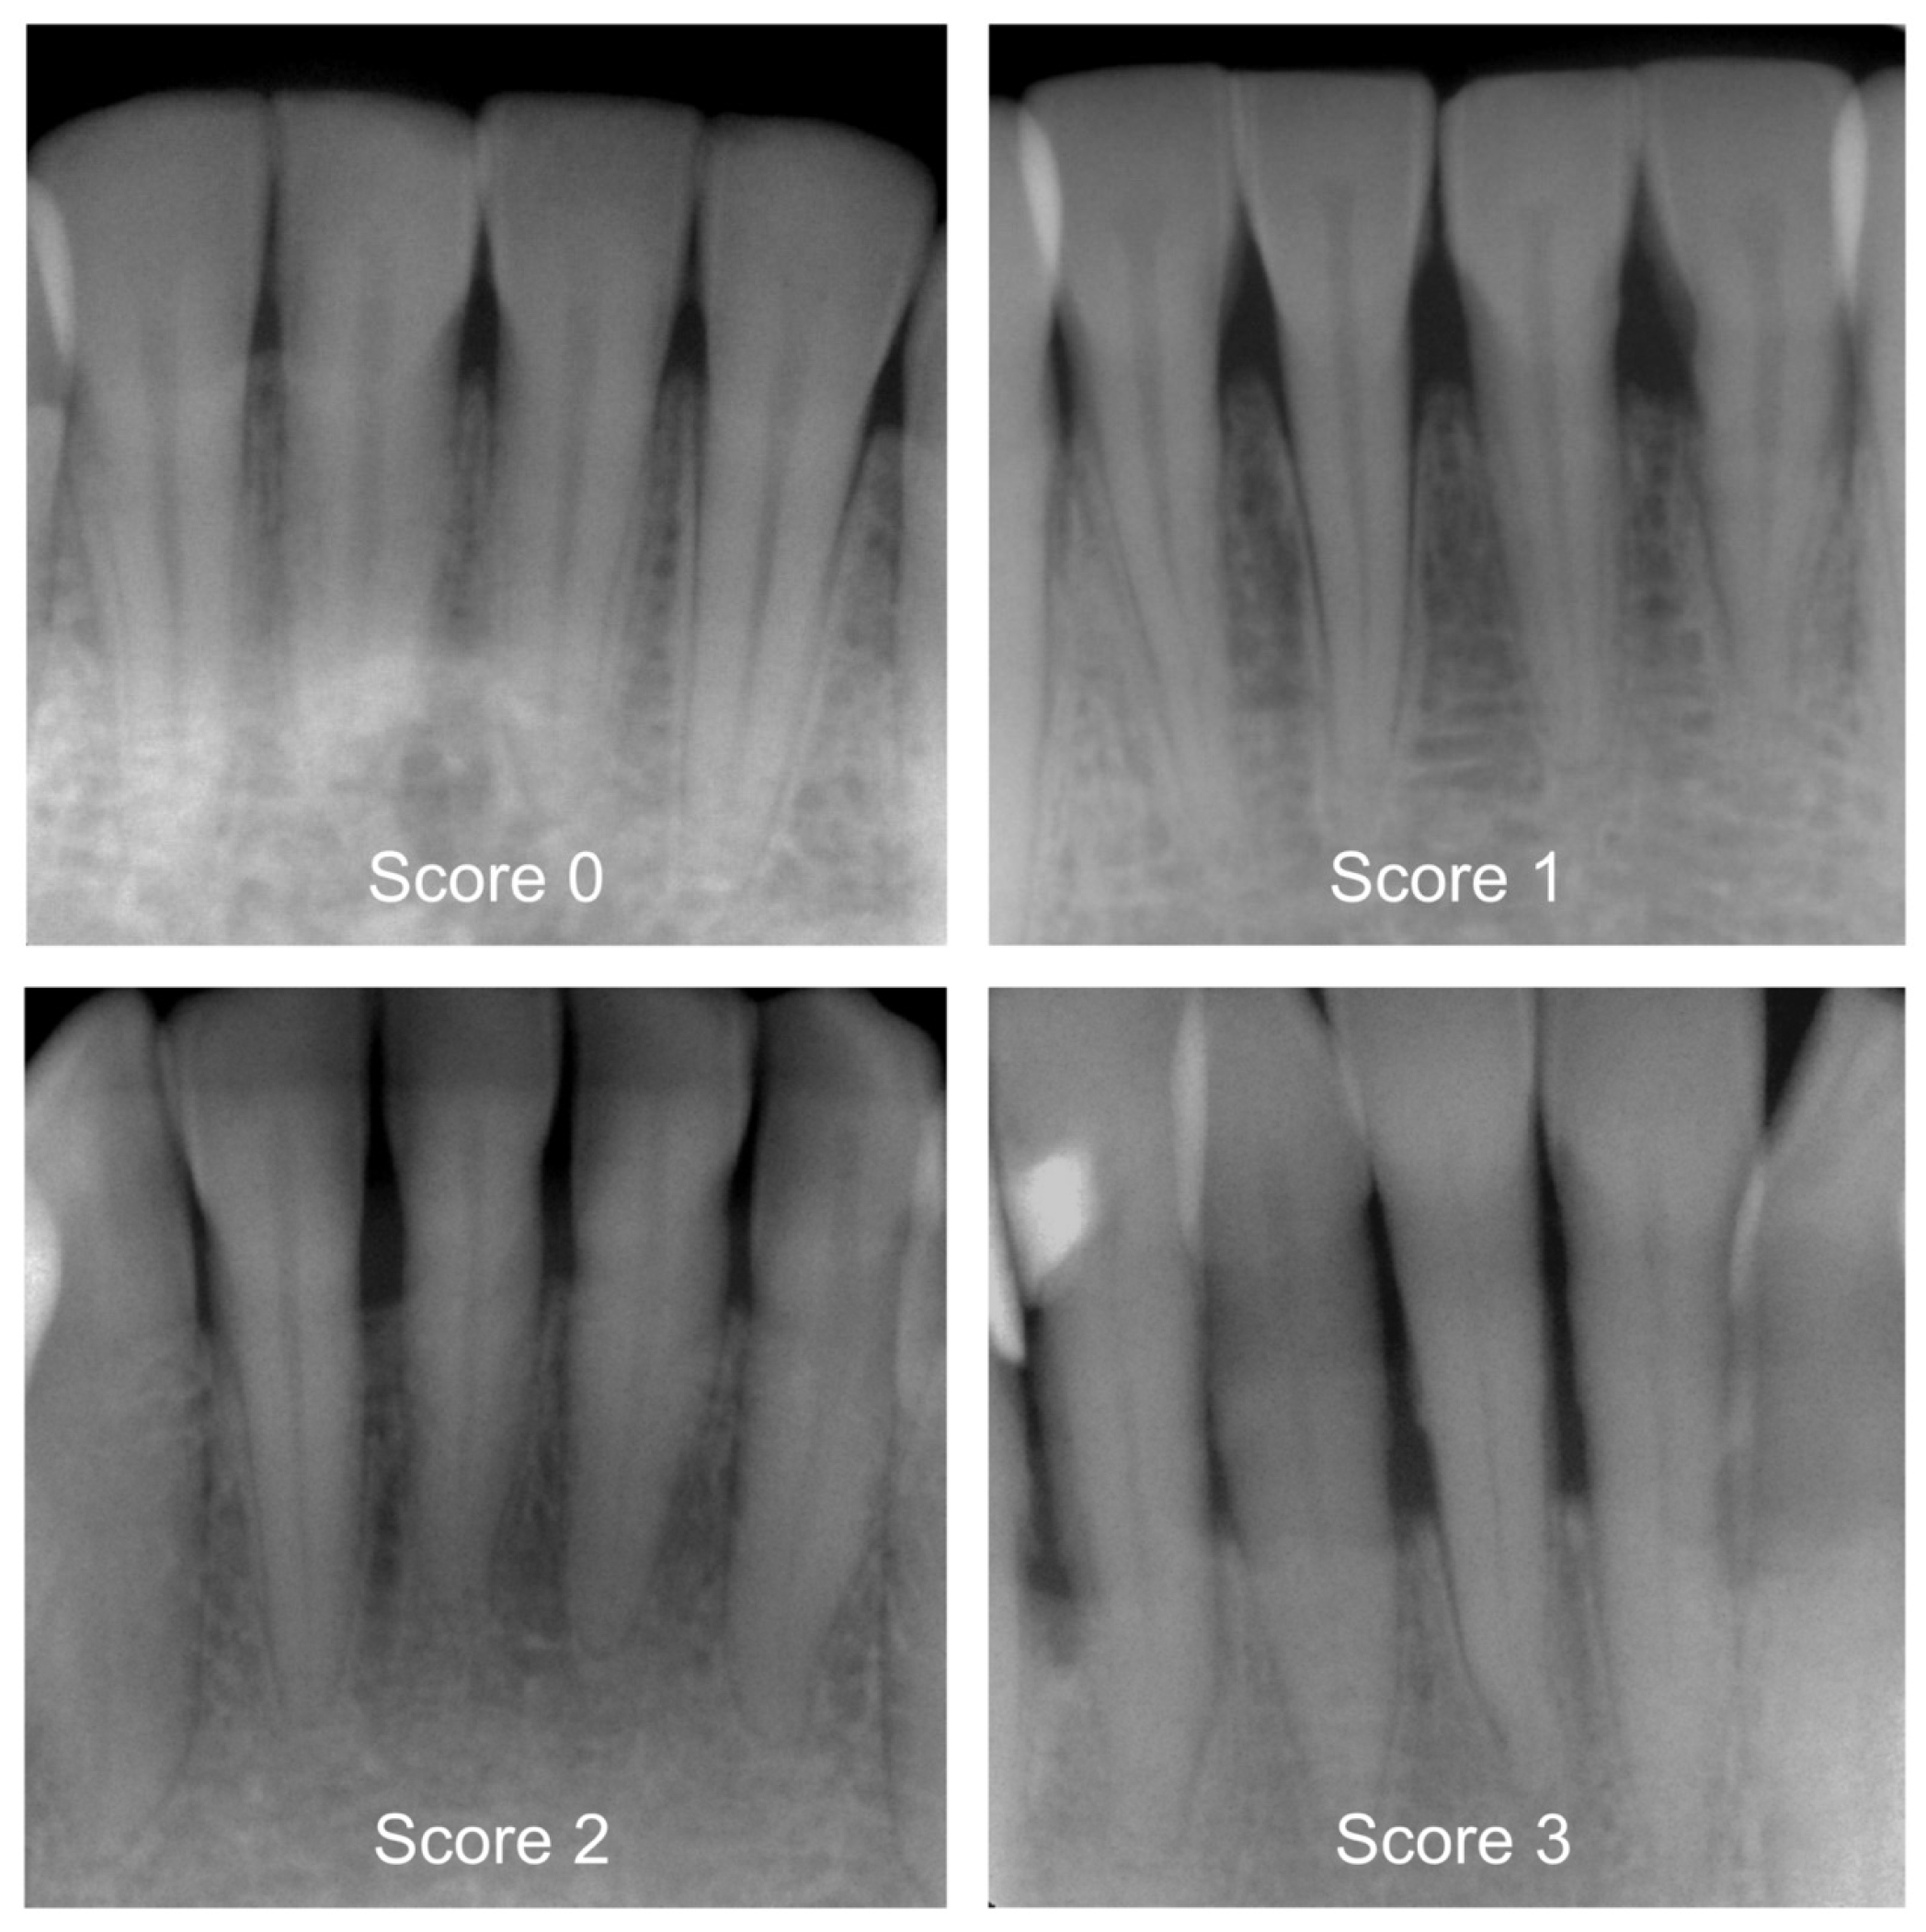

Prior to the start of the study, a two-day workshop was held by the principal investigator (J.K.), during which the group of participating dentists (N = 7) was trained. In addition, the efficiency of the training was determined during a calibration course. Reproducibility of PBL within and between investigators was assessed using 150 periapical radiographs, and the corresponding inter- and intra-examiner reliability showed substantial kappa values [17]. The detailed kappa values are specified in Table 1. A group of graduated dentists (P.H., T.M., A.W., L.M.) then pre-categorized all X-rays by differentiating between healthy periodontium and mild, moderate, or severe PBL [13,14]. Following this, more clinically experienced examiners (H.D., U.W., J.K.) independently counterchecked each diagnostic decision. More specifically, these diagnostic criteria and ratings were applied: 0—healthy periodontium, PBL not detectable, 1—mild radiographic PBL up to 15% in the coronal third of the tooth, 2—moderate radiographic PBL between 15% and 33% of the root length, and 3—severe radiographic PBL beyond the coronal third of the tooth (Figure 1). In case of differing diagnostic opinions, each image was subject to continued discussion until consensus was achieved. The use of anonymized periapical radiographs meant that no further clinical information could have been acquired to make a diagnostic decision. One dichotomized diagnosis decision (0 vs. 1–3) was made for each X-ray, which consequently became the reference standard for the cyclic training and the repeated evaluation of the AI-based CNN.

Figure 1.

Examples of periapical radiographs for all categories: healthy periodontium, periodontal bone loss (PBL) not detectable (Score 0), mild radiographic PBL up to 15% in the coronal third of the tooth (Score 1), moderate radiographic PBL between 15% and 33% of the root length (Score 2), and severe radiographic PBL beyond the coronal third of the tooth (Score 3).